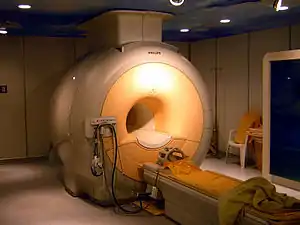

MRI scanner

Construction and operation

The major components of an MRI scanner are: the main magnet, which polarizes the sample, the shim coils for correcting inhomogeneities in the main magnetic field, the gradient system which is used to localize the MR signal and the RF system, which excites the sample and detects the resulting NMR signal. The whole system is controlled by one or more computers.

Magnet

The magnet is the largest and most expensive component of the scanner, and the remainder of the scanner is built around it. The strength of the magnet is measured in teslas (T). Clinical magnets generally have a field strength in the range 0.1–3.0 T, with research systems available up to 9.4 T for human use and 21 T for animal systems.[42] In the United States, field strengths up to 7 T have been approved by the FDA for clinical use.[43]

Just as important as the strength of the main magnet is its precision. The straightness of the magnetic lines within the center (or, as it is technically known, the iso-center) of the magnet needs to be near-perfect. This is known as homogeneity. Fluctuations (inhomogeneities in the field strength) within the scan region should be less than three parts per million (3 ppm). Three types of magnets have been used:

- Superconducting electromagnet: When a niobium-titanium or niobium-tin alloy is cooled by liquid helium to 4 K (−269 °C, −452 °F) it becomes a superconductor, losing resistance to flow of electric current. An electromagnet constructed with superconductors can have extremely high field strengths, with very high stability. The construction of such magnets is extremely costly, and the cryogenic helium is expensive and difficult to handle. However, despite their cost, helium cooled superconducting magnets are the most common type found in MRI scanners today.

Most superconducting magnets have their coils of superconductive wire immersed in liquid helium, inside a vessel called a cryostat. Despite thermal insulation, sometimes including a second cryostat containing liquid nitrogen, ambient heat causes the helium to slowly boil off. Such magnets, therefore, require regular topping-up with liquid helium. Generally a cryocooler, also known as a coldhead, is used to recondense some helium vapor back into the liquid helium bath. Several manufacturers now offer 'cryogenless' scanners, where instead of being immersed in liquid helium the magnet wire is cooled directly by a cryocooler.[44] Alternatively, the magnet may be cooled by carefully placing liquid helium in strategic spots, dramatically reducing the amount of liquid helium used,[45] or, high temperature superconductors may be used instead.[46][47]

Magnets are available in a variety of shapes. However, permanent magnets are most frequently C-shaped, and superconducting magnets most frequently cylindrical. C-shaped superconducting magnets and box-shaped permanent magnets have also been used.

Magnetic field strength is an important factor in determining image quality. Higher magnetic fields increase signal-to-noise ratio, permitting higher resolution or faster scanning. However, higher field strengths require more costly magnets with higher maintenance costs, and have increased safety concerns. A field strength of 1.0–1.5 T is a good compromise between cost and performance for general medical use. However, for certain specialist uses (e.g., brain imaging) higher field strengths are desirable, with some hospitals now using 3.0 T scanners.